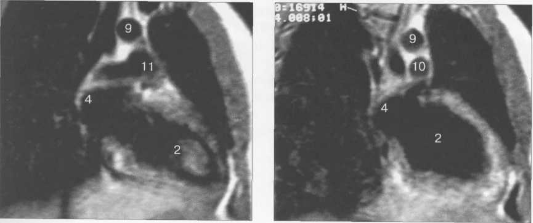

Рис. 9.48. MPT сердца. Сагиттальная плоскость.

Рис. 9.49. МРТ сердца. Двухкамерные сечения.

Рис. 9.50. МРТ сердца. Фронтальные сечения.

Рис. 9.51. МРТ сердца. Сечения по короткой оси левого желудочка.

Рис. 9.52. МРТ сердца. Четырехкамерные сечения.

На рис. 9.47—9.52 представлены Т1-ВИ наиболее часто используемых МР-сечений сердца.

Здесь и на рис. 9.48—9.52:

I — правый желудочек, 2 — левый желудочек, 3 — правое предсердие, 4 — левое предсердие, 5 — межжелудочковая перегородка, 6 — межпредсердная перегородка, 7 — задняя стенка левого желудочка, 8 — восходящая часть аорты, 9 — дуга аорты, 10 — нисходящая часть аорты, 11 — легочный ствол, 12 — правая легочная артерия. 13 — левая легочная артерия, 14 — верхняя полая вена, 15 — нижняя полая вена, 16 — трахея.